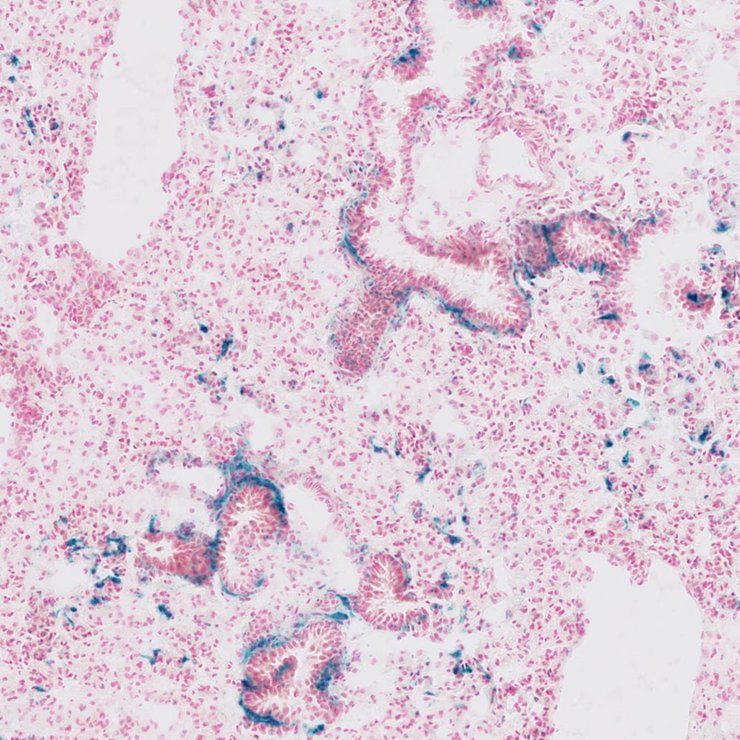

Specimen JAX_1799265: postnatal adult; Pcsk5tm1b(KOMP)Mbp/Pcsk5+ (more )

Structure Level Pattern Image Note

TS28: lung Present JAX_1799265